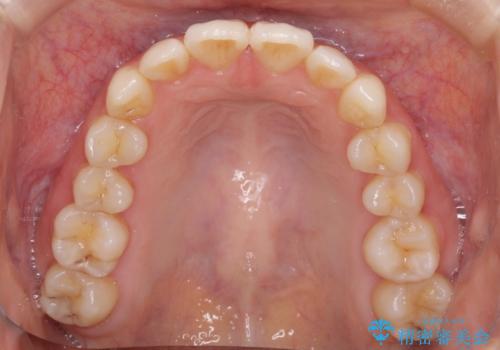

- 前歯のデコボコを気にして来院された患者様です。

叢生と捻転が随所に認められるものの、マウスピースで十分対応可能であったため、インビザラインにて矯正治療を行うこととしました。

マウスピース矯正は毎日しっかりと装着することがとても大切です。

こちらの方はしっかりと指示を守って装着してくださったため、予定通り治療を終えることができました。